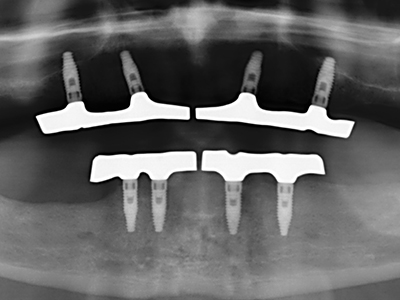

El tejido óseo no solo tiene un contenido puramente mineral, sino que también presenta una importante proporción de fibras de colágeno. Esto no solo garantiza una buena resistencia a la presión, sino también una cierta flexibilidad, que puede aprovecharse para la realización de aumentos. En la plastia de expansión clásica a efectos de una partición ósea, la cresta maxilar atrofiada se divide en su eje longitudinal y, tras alcanzar una profundidad de osteotomía suficiente, se extiende con cuidado (fig. 13-16), en un caso ideal sin desperiostizar de forma visible el maxilar (Brugnami, Caiazzo et al. 2014, Stricker, Fleiner et al. 2014). Los sistemas de tornillos y placas con distancia de expansión creciente han demostrado su eficacia para distanciar entre sí las dos tablas óseas por debajo del umbral de rotura. Por regla general, se requieren anchuras de hueso residual de al menos 3 a 4 mm (Chiapasco, Zaniboni et al. 2006) para garantizar una flexibilidad y una cobertura ósea suficientes de los implantes que van a incorporarse. En caso necesario, una osteotomía de descarga vertical unilateral o bilateral puede mejorar la flexibilidad. Como alternativa a la técnica clásica se ha descrito una combinación con otras técnicas de aumento, sobre todo en la parte bucal.

Con el uso de sierras piezoeléctricas la división se efectúa de forma especialmente cuidadosa y sin pérdidas importantes de las dimensiones, por lo que no se han encontrado diferencias significativas entre los implantes realizados en el maxilar dividido y en la cresta alveolar no deficitaria (Chiapasco, Zaniboni et al. 2006, Danza, Guidi et al. 2009). No obstante, precisamente en la partición profunda y limitada de forma local, es preciso asegurarse de que exista una adecuada irrigación por agua para evitar que se produzcan sobrecargas térmicas en las áreas de osteotomía apical.